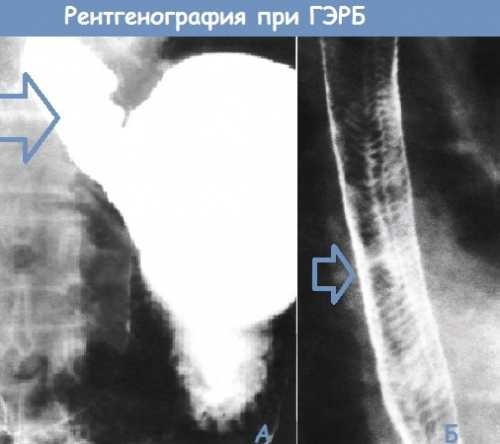

К сожалению, выраженность клинических проявлений далеко не в полной мере отражает выраженность рефлюкса. Более чем в случаев эпизоды снижения внутрипище водной кислотности ниже не сопровождается какимилибо ощущениями. Оценка изменений пищевода при гастроэзофагеальной рефлюксной болезни посредством эзофагос копии с биопсией позволяет не только оценить степень поражения пищевода, но и провести дифференциальный диагноз с эзофагитами. Рентгено логическое исследование пищевода с барием позволяет выявить анатомических нарушений пищевода и желудка, которые способствуют формированию гастроэзофагеального рефлюкса грыжа пищеводного отверстия диафрагмы. часовое мониториро вание внутрипище водной кислотности играет важную роль в подтверждении наличия гастроэзофагеального рефлюкса. Лечебные мероприятия при гастроэзофагеальной рефлюксной болезни должны быть направлены на уменьшение выраженности рефлюкса, снижение повреждающих свойств желудочного содержимого, повышение пищеводного очищения, защиту слизистой оболочки пищевода. Важно соблюдение общих мер, которые способствуют уменьшению выраженности заброса желудочного содержимого в пищевод. Они включаютнормализацию массы тела у больных с избыточной массой тела эта мера позволяет уменьшить выраженность степень недостаточности нижнего пищеводного сфинктера исключение курения, уменьшение потребления алкоголя, ограничение потребления жирной пищи, кофе, шоколада перечисленные воздействия способствуют снижению тонуса нижнего пищеводного сфинктера, жирная пища замедляет активность желудка исключение кислой пищи, которая, как правило, провоцирует появление изжогиприем пищи небольшими порциями, регулярно прием пищи не позднее, чем за часа до снаизбегание нагрузок, связанных с повышением внутри брюшного давлениясон на кровати, головной конец которой приподнят на см. Подробнее о диете при эзофагитах. При неэффективности подобных мероприятий назначают антациды. Антациды группа лекарственных средств, содержащих в своем составе соли алюминия, магния, кальция, которые нейтрализуют соляную кислоту. Помимо этого, антациды способны связывать и снижать активность пищеварительного фермента желудочного сока, желчные кислоты и лизолецитин входящие в состав желчи и обладающие повреждающим действием на слизистую желудка и пищевода. Предпочтительнее принимать антацидные препараты в форме гелей.